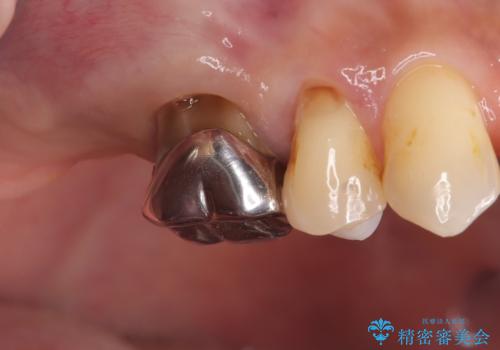

- 治療計画

- 患者様は、右側の奥歯でしっかり噛めないことを主訴に来院されました。診察の結果、右上6・右下6の根管治療が不十分で、感染のリスクがある状態と判断。これらの歯は再根管治療を行い、セラミッククラウンで補綴することにしました。また、右上7・右下7は欠損しており、噛み合わせを回復するためにインプラント治療を計画しました。